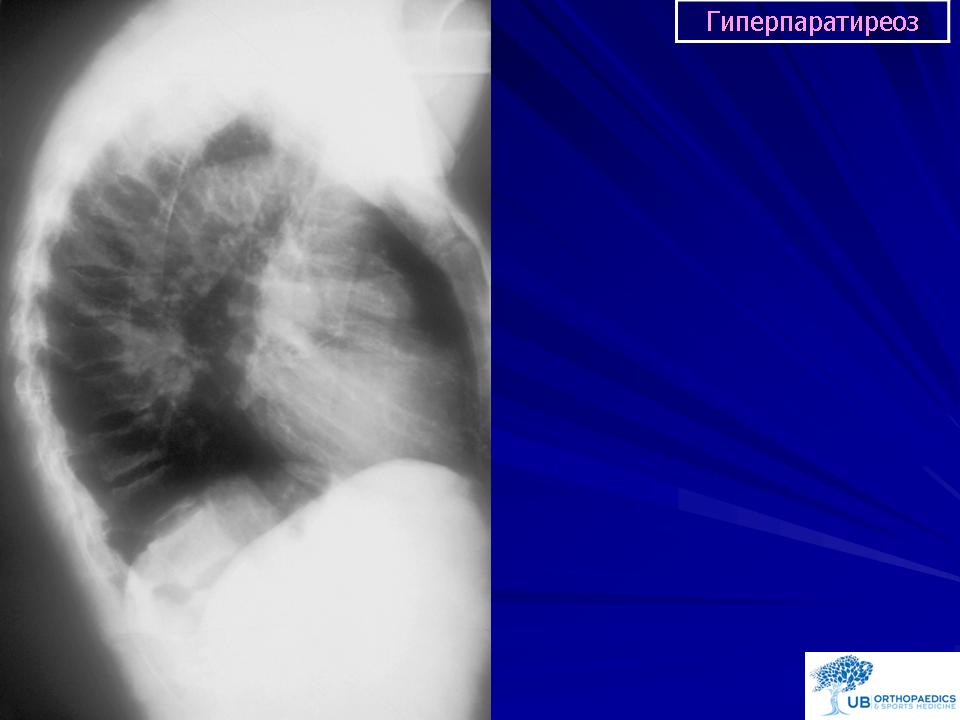

На рентгенограммах определяется перестройка костной структуры в виде очагового или диффузного крупнозернистого остеопороза. Характерна кистозная перестройка костной структуры. Кисты располагаются, как в зоне костномозгового канала, так и интракортикально. Форма их - овальная, вытянутая по длиннику кости. Кисты могут быть одиночными и множественными. Часто кисты сливаются одна с другой и в зоне костномозгового канала они имеют нечеткие контуры.

В плоских костях также отмечается истончение коркового слоя, остеопороз, кистовидные дефекты. В телах позвонков выражен остеопороз. Постепенно краниальные и каудальные пластинки вдавливаются, развиваются «рыбьи позвонки». В телах позвонков могут выявляться мелкие, сливного характера кисты. При этом сохраняется тонкий кортикальный слой. Межпозвонковые диски в процесс не вовлекаются в связи, с чем высота их не уменьшается.